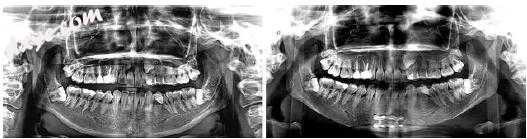

图10.4术前全景放射照片(左)。术后1天随访X光片(右)